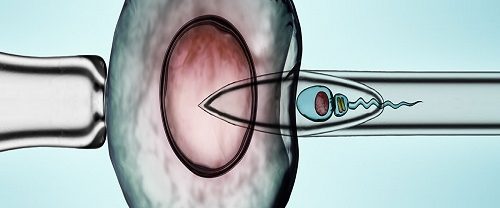

Tüp Bebek Tüp bebek, doğal yollarla gebe kalmakta zorluk yaşayan çiftlere yardımcı olmak amacıyla uygulanan bir tedavi yöntemidir. İşlem genellikle aşağıdaki adımları içerir: Yumurtalık Uyarımı: Tüp bebek tedavisinin ilk adımı, kadının yumurtalıklarının uyarılmasıdır. Bu, hormonal ilaçlar kullanılarak gerçekleştirilir. Hormon ilaçları, yumurtalıkların birden fazla yumurta üretmesini sağlar. Normalde kadın her ay bir tane yumurta üretirken, bu…

IVF İn Vitro Fertilizasyonun Temel İlkesi IVF İn Vitro Fertilizasyon, doğal olarak gebe kalamayan çiftlere yardımcı üreme teknikleri arasında en yaygın kullanılan yöntemlerden biridir. Temel ilkesi, gametlerin (yumurta ve sperm) laboratuvar ortamında bir araya getirilerek döllenmelerinin sağlanması ve oluşan embriyoların rahim içine transfer edilerek gebelik elde edilmesidir. İn vitro fertilizasyon süreci, bir dizi aşamadan oluşur:…

Embriyo Genetik Tanısı Nedir? Embriyo Genetik Tanısı, preimplantasyon döneminde embriyoların genetik yapılarının incelenmesi ve değerlendirilmesi işlemidir. Bu tanı yöntemi, genetik hastalıkların tespit edilmesi, tekrarlayan düşüklerin önlenmesi, ileri yaşan anne adaylarında genetik riskin azaltılması ve cinsiyet seçimi gibi amaçlarla uygulanır. Embriyo Genetik Tanısının birinci amacı, genetik hastalıkların tespit edilmesidir. Bazı çiftler, genetik hastalık taşıyıcısı olabilir ve…